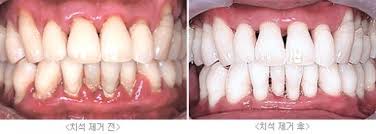

| 치은염 | 잇몸 붉어짐, 출혈 동반 | 스케일링, 위생관리 |

💧 구강 청결 관리 팁

- 부드러운 칫솔과 치간칫솔, 치실을 병행해 치태 제거